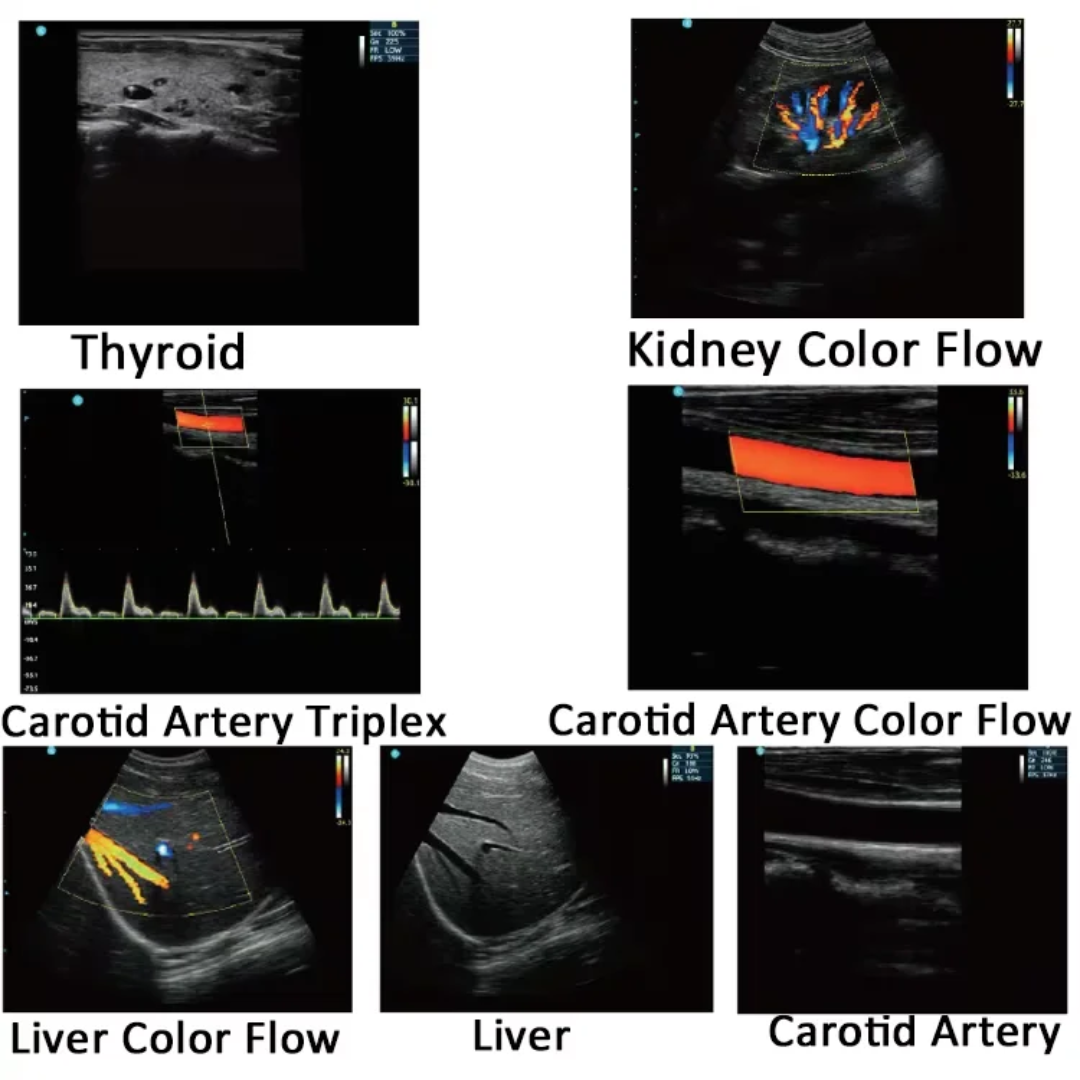

🏥 Clinical Applications of the DAWEI DW-580

The DAWEI DW-580 Laptop B/W Diagnostic Ultrasound Device is widely applicable in various clinical specialties, including:

-

Abdomen: Liver, spleen, kidney, gallbladder, and pancreas imaging.

-

Obstetrics & Gynecology: Pregnancy monitoring, fetal growth, uterine, and ovarian exams.

-

Urology: Bladder and prostate evaluations.

-

Pediatrics: Non-invasive scanning of infant organs and pediatric tissues.

-

Vascular: Examination of veins and arteries for blood flow assessment.

-

MSK (Musculoskeletal): Evaluation of muscles, tendons, and joints for injury or disease.

With its versatility, the DW-580 is suitable for both clinical and point-of-care settings, making it a cost-effective diagnostic tool for private practices, rural clinics, and hospital departments.